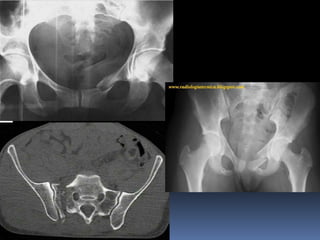

Rx Disyunción sacroilíaca y fractura de las ramas púbicas izquierdas

(flechas) por cizallamiento vertical.

Varón de 14 a. Accidente de motocicleta. Se realizó tratamiento quirúrgico mediante

fijaciones internas con tornillos en la articulación SI izquierda e inmovilización pélvica

con un tutor externo

Fractura tipo C2 : Fractura bilateral del sacro (completa del ala sacra izquierda e

incompleta de la derecha) por cizallamiento vertical en una mujer de 29 años.